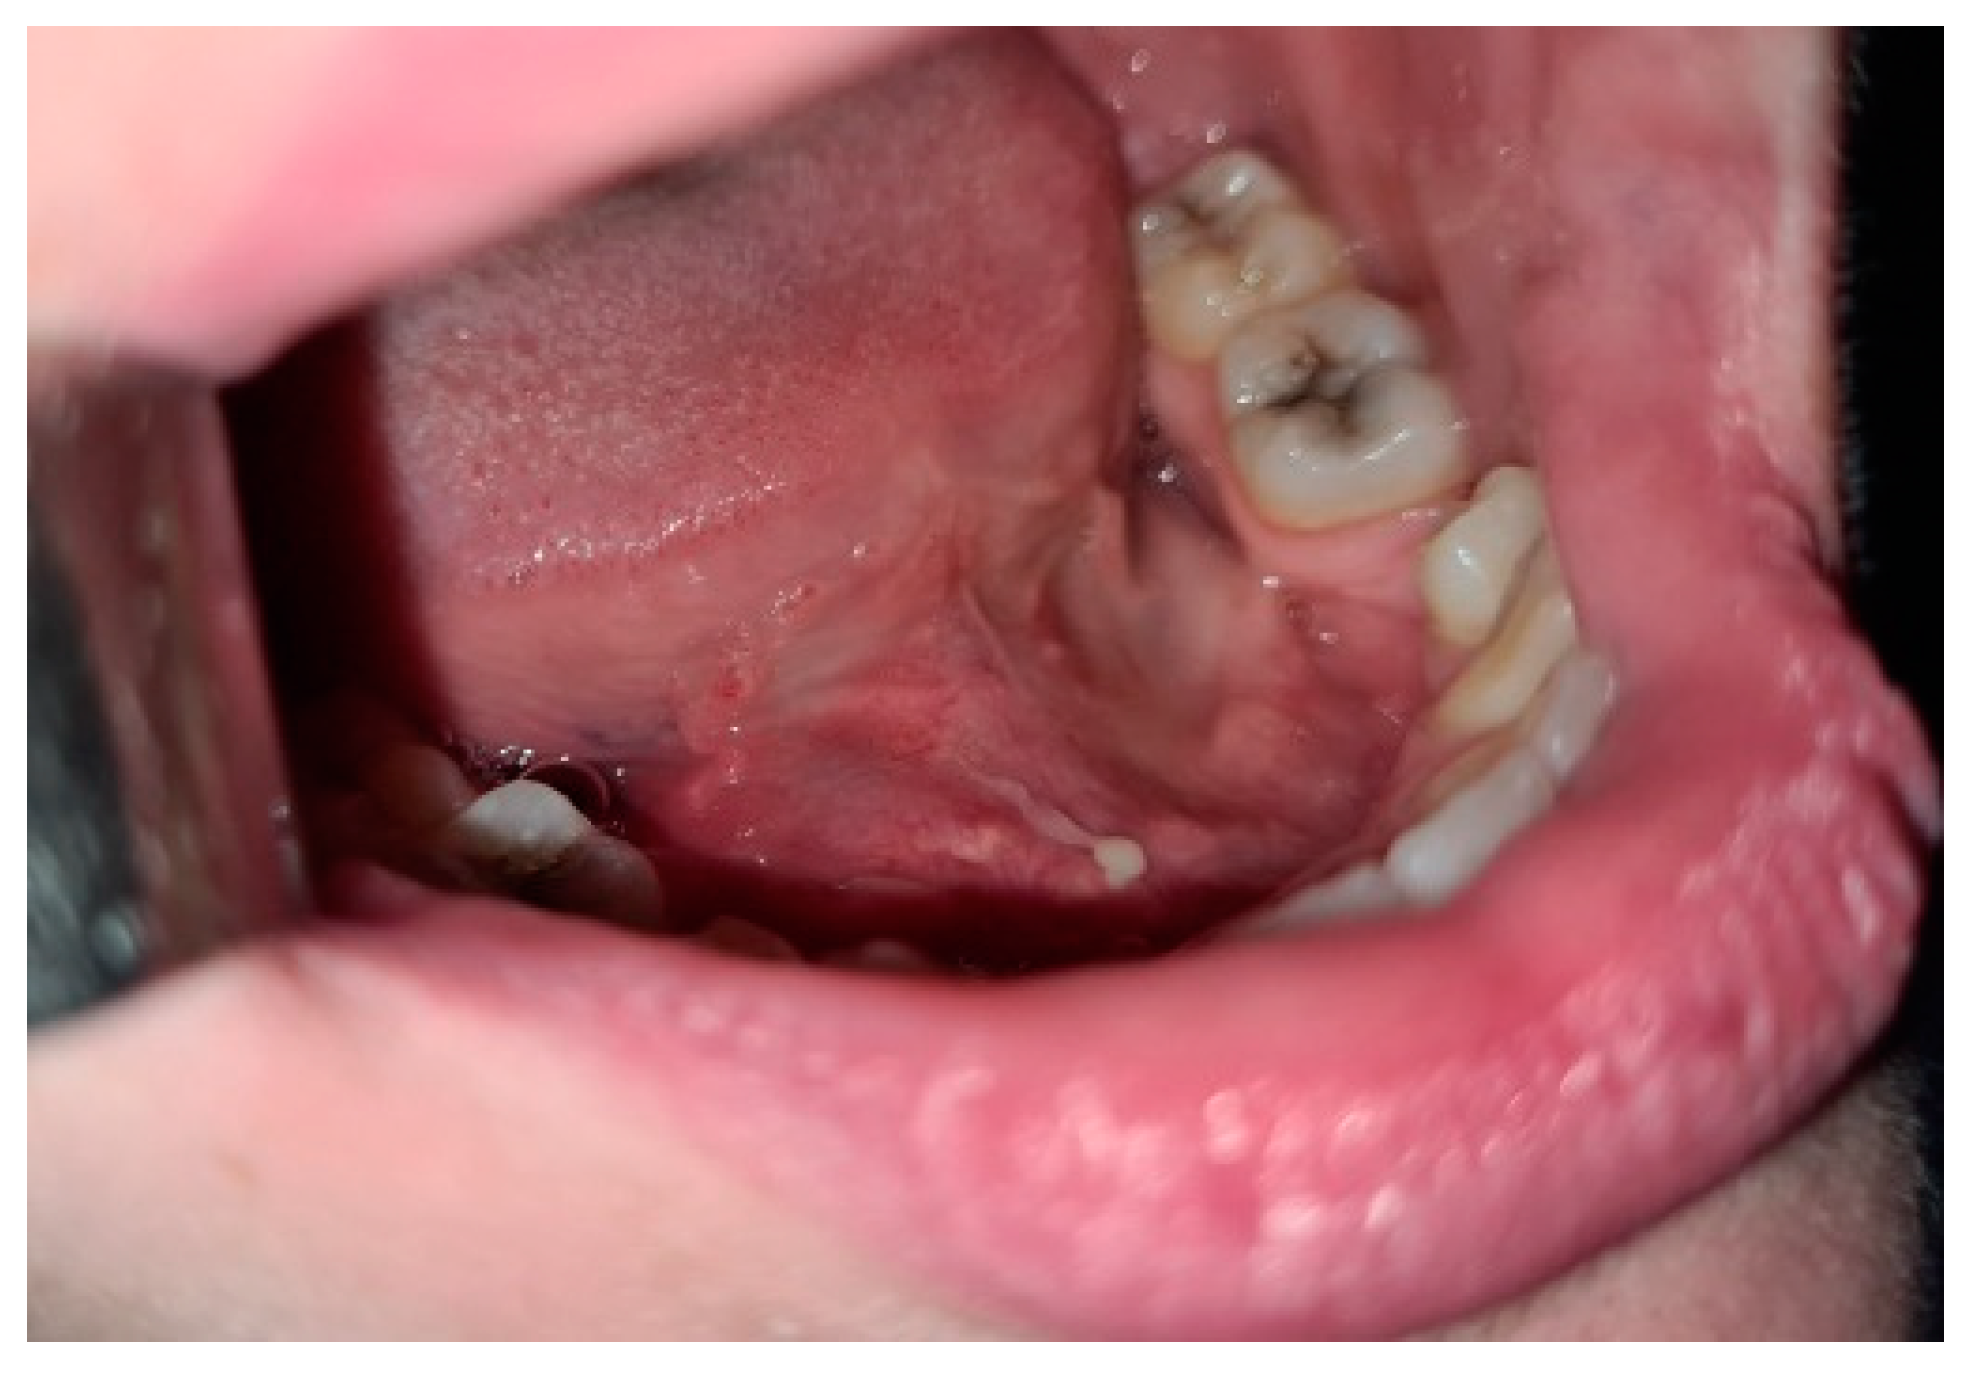

Multiple Faces of Cervical Lesions in Children

2. Case Report